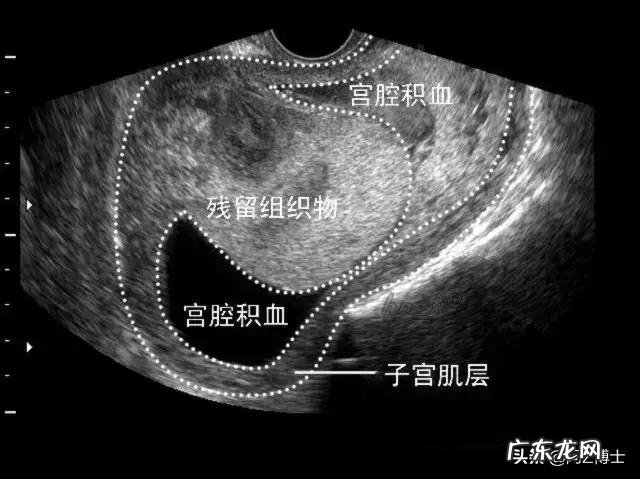

二.产后出血和晚期产后出血的治疗措施?产后出血必须对因治疗,通过原因对比可见,产后出血主要原因在于宫缩乏力,而胎盘胎膜残留是次要原因;但是晚期产后出血的原因中胎盘胎膜残留就是主要原因,通常24小时之前如果因为宫缩欠佳引起出血,早就进行了治疗,所以晚期产后出血很少会造成产妇死亡的 。产后出血主要采取宫缩抑制剂,如缩宫素最普遍;晚期产后出血如果是胎盘胎膜残留引起,需要进行清宫止血 。